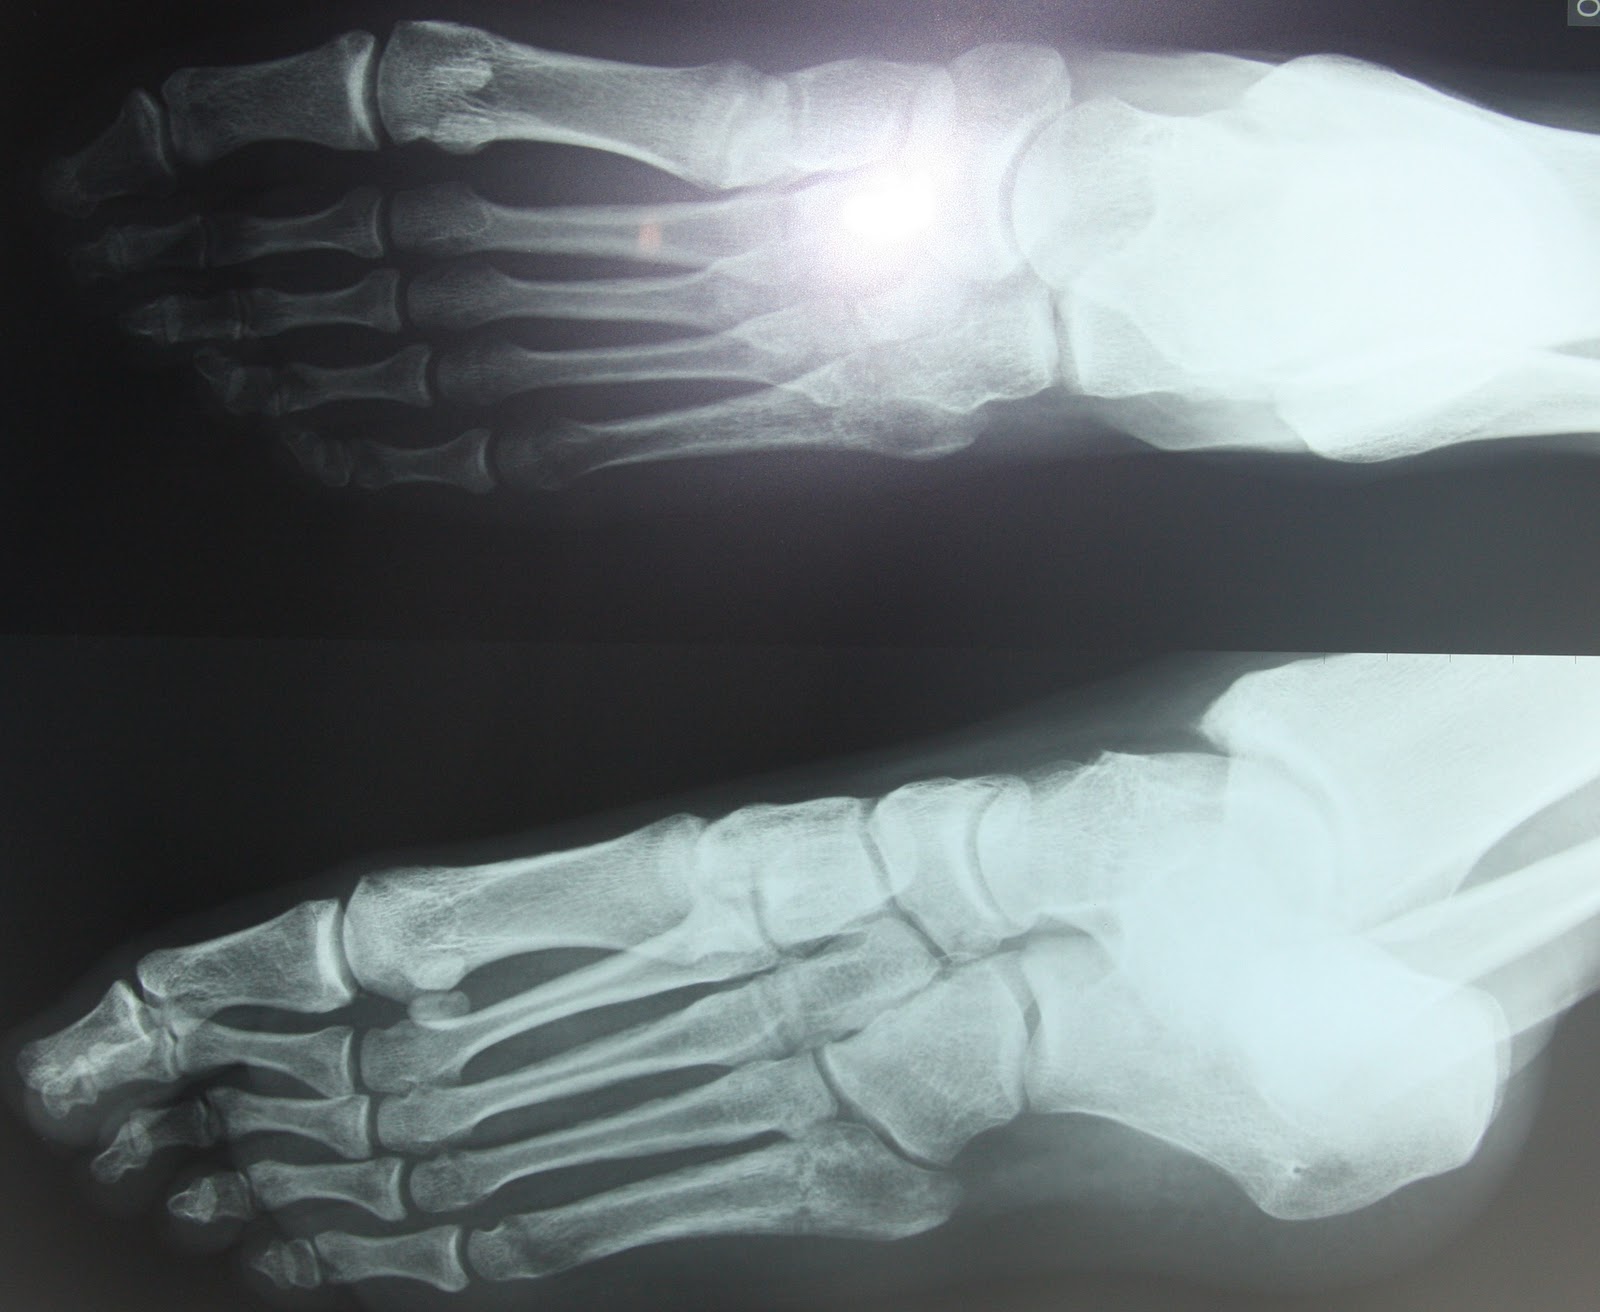

Le fratture da stress metatarso erano originariamente definite fratture da marcia , perché erano comuni tra i soldati all'inizio del xix secolo. Il piede non si presenta gonfio e non vi è limitazione nel movimento, ma.

Basso rischio e alto rischio. Le fratture da stress del quinto metatarso sono le più difficili da guarire e sono più probabili richiedere un intervento chirurgico. Nonostante ciò, non è detto che una frattura da stress.

Fratture da stress del piede.

Le fratture da stress si riferiscono a fratture che si verificano nell'osso a causa della mancata alberi metatarso dal 2 ° al 4 °. Marzo 13th, 2016 by admin. Nella pallamano, la frattura della prima costola è più. La gravità delle fratture da stress è dovuta al fatto che tessuti a metabolismo lento (come ossa e tendini) hanno un processo riparativo più lungo rispetto ai muscoli e spesso. La frattura da stress si verifica di solito nell'ii metatarso. Salve, le scrivo per un problema che mi afflligge da ormai 50 giorni, durante gli allenamenti ho riportato una frattura diafisaria da stress al iii metatarso (la prima rx era negativa e l ortopedico ha pensato cosi a una metatarsalgia dovuta a piede cavo(effettuate due infiltrazioni steroidee e plantare con. Nonostante ciò, non è detto che una frattura da stress. Il piede non si presenta gonfio e non vi è limitazione nel movimento, ma. Frattura da stress la frattura da stress colpisce principalmente i pazienti giovani e gli atleti, soprattutto all'inizio della stagione sportiva. Le fratture da stress sono lesioni che colpiscono soprattutto chi pratica in modo continuativo un'attività sportiva molto intensa. La frattura quinto metatarso è per definizione la rottura traumatica o non traumatica della base prossimale del quinto metatarso del piede. La maggior parte di esse colpisce le strutture ossee dell'arto inferiore e si manifestano soprattutto negli atleti che praticano la corsa. A seconda dello sport, diverse località si incontrano più frequentemente. Lazio, il portiere albanese si trascinerebbe questo problema: Alcune donne e ragazze che eseguono allenamenti pesanti sono affette da una sindrome nota come triade dell'atleta le fratture da stress possono non essere osservabili all'esame radiografico se sono piccole oppure se la radiografia è stata acquisita subito dopo il. Domanda 1) se io mi comportassi come se ci fosse una frattura da stress (non ho eseguito altri esami oltre rx) , dovrei comunque immobilizzare il piede con. Fratture da stress normalmente guariscono senza complicazioni e, col tempo, le persone sono in grado di tornare completamente alle loro attività precedenti.